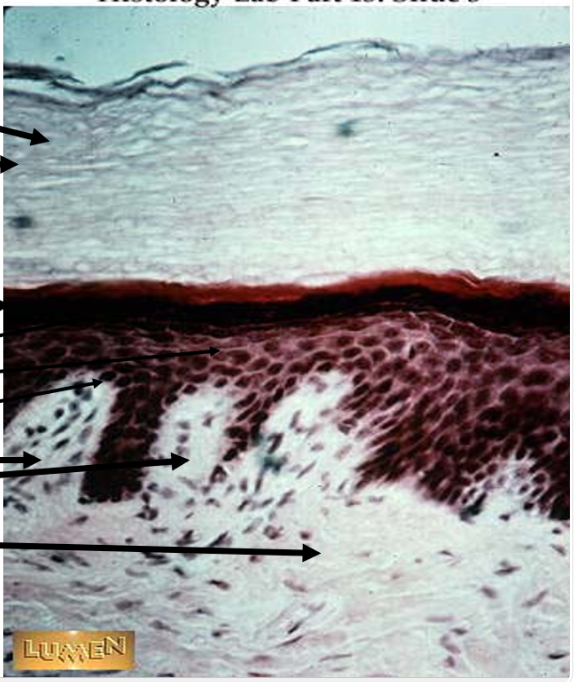

the purple is

outer dead cells being sloughed off (squamous)

the dark blue is

stratum lucidium

the green is

stratum granulosum

the yellow is

stratum spinosum

the orange is

stratum basale

the red is

dermal papillae

the black is

loose irregular connective tissue of dermis

the light blue is

stratum corneum